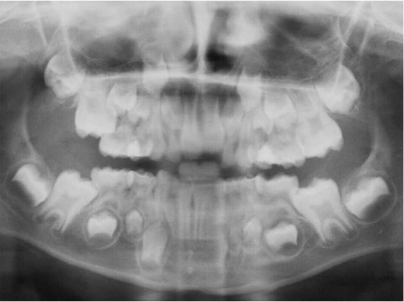

What is this positioning error?

Spine not straight

- no bite peg used (overlapping of teeth)

- Kyphosis of the spine or theyre not positioned correctly + neck is extended forwardly

- See a big white image right in the middle = ghost image of the spine

- Spine blocked the xray

- Teeth are also overlapped